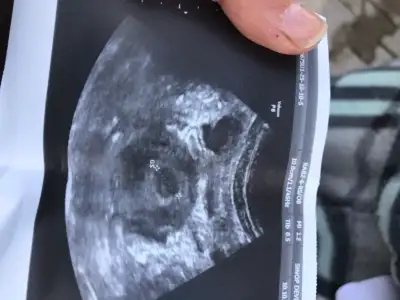

Gebelik testime bakar mısınız

Maşallah kesede görülmüş sağlıcakla kucağına almayı nasip etsin rabbim Rabbim analı babalı büyütsün

Ay inşallah kese oluşmuş ama daha belli olmaz erken dedi 2 hafta sonra tekrar gidicem o zaman kalp atışını duyarız dedi inşallah duyarız sorun çıkmaz